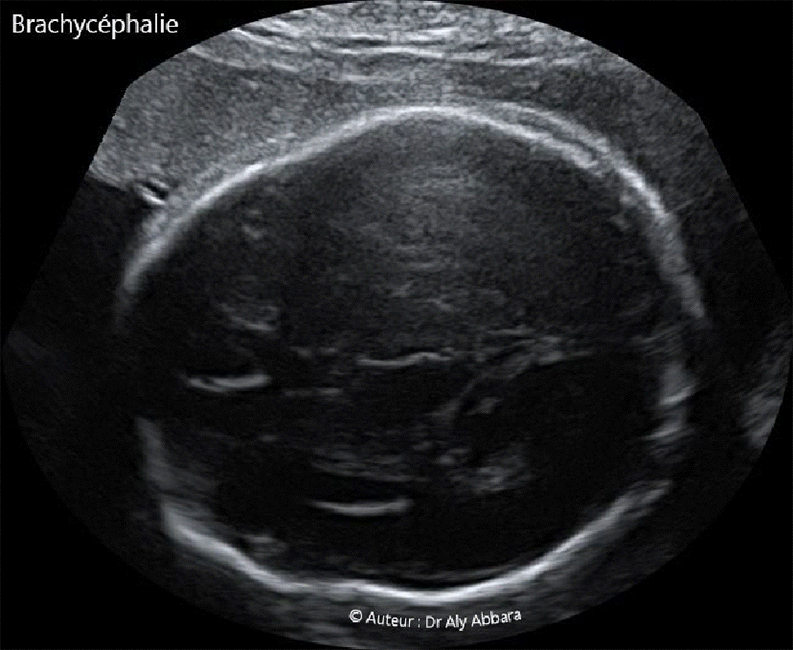

Images échographiques montrant un crâne fœtal brachycéphale (à 26 SA).

Index céphalique = 87

A comparer aux crânes dolichocéphales

Description : Il s'agit d'un crâne court d'avant en arrière avec parfois l'impression d'un crâne tronqué en arrière, dans la région occipitale ; la plus grande longueur (diamètre occipito-frontale) l'emporte de peu sur la plus grande largeur (diamètre bipariétal).